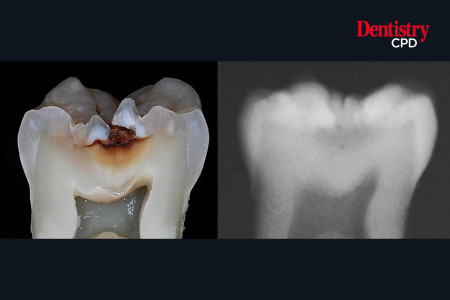

AI and caries detection